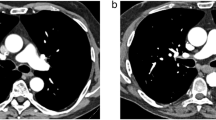

All CTPAs in both groups were of diagnostic image quality. For 60 keV images, the CTPA image quality was considered excellent or good in 31/32/32/30 cases (96.9%/100%/100%/93.8%; R1/R2/R3/R4) in the PCD group and in 31/30/32/30 cases (96.9%/93.8%/100%/93.8%) in the EID group. An image example is given in Fig. 1, demonstrating CTPA with bilateral pulmonary embolism with PCD and EID at 60 keV. For T3D/blended images, the CTPA image quality was rated as excellent or good in 30/32/28/29 cases (93.8%/100%/87.5%/90.6%) in the PCD group and in 31/32/32/30 cases (96.9%/100%/100%/93.8%) in the EID group. For each group, the overall percentage of CTPAs rated with a subjective image quality score of “1” or “2,” indicating excellent or good image quality, was calculated with the following results: in the PCD group, 93.8% of 60 keV CTPAs and 90.6% of T3D CTPAs were rated with a subjective image quality score of “1” or “2,” while in the EID group 84.4% of 60 keV CTPAs and 90.6% of blended (120 kV) CTPAs were rated with a subjective image quality score of “1” or “2.” Subjective evaluation of image quality is summarized in Table 4.

PCD-CT (a, b) and EID-CT (c, d) demonstrating bilateral pulmonary embolism. Dual-energy EID-CT exhibits significant pulsation artifacts (c; arrow) and blurring of thrombus material (c; arrowheads) compared with high-pitch 60-keV PCD-CT. Despite application of a low-dose protocol, PCD-CT delivers excellent intraluminal contrast, paired with high image sharpness and delineation of the thrombus material (a, b; arrows). PCD-CT, photon-counting detector CT; EID-CT, energy-integrating detector CT

Subjective image quality was considered best by all readers for 60 keV PCD examinations with excellent or good ratings in 93.8% of PCD-CTPAs. The main reason for higher subjective image ratings in the PCD group was lower susceptibility to motion and especially breathing artifacts. In other words, images derived from conventional EID-based dual-energy CT often appear blurry (Fig. 1). Technically, this is mainly due to the fact that the helical pitch factor for dual-energy acquisitions on conventional EID scanners is limited by the vendors (in case of the EID system used in this study default setting of 0.55), whereas the PCD-equipped scanner allows for multi-energy data acquisition with higher pitch factors (2.0 in our study setting) associated with significantly shorter scan times. This issue is especially advantageous for patients who have difficulty following breath-holding commands due to dyspnea, which would be a quite expected symptom in patients presenting with pulmonary embolism [1]. No CTPA examination was deemed “non-diagnostic” on either scanner, irrespective of the acquisition or reconstruction settings.